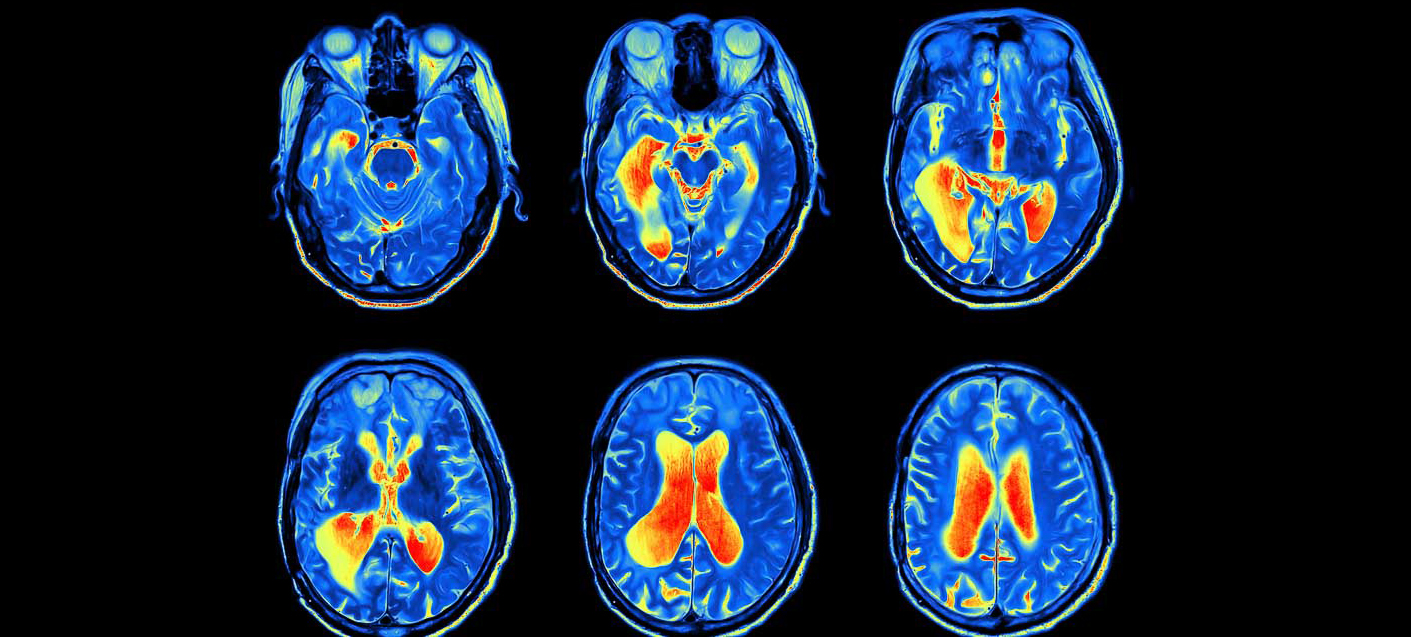

Surgeries have evolved over the past few years. Michael Vogelbaum, M.D., Ph.D., (program leader of Neuro-Oncology and chief of Neurosurgery at Moffitt) is a leader in the field. He has a program in drug delivery that delivers drugs directly into tumors to overcome the issues with the blood-brain barrier to deliver new treatments. Things have changed surgically in terms of imaging, detecting tumor cells in the operating room and making sure surgeons get all the tumor cells without affecting the normal cells of the brain. He also emphasizes evidence-based neurosurgical care where we do trials to understand if one approach is better than another. We want to provide the best care driven by data so you know you’re doing the best thing for the patient.